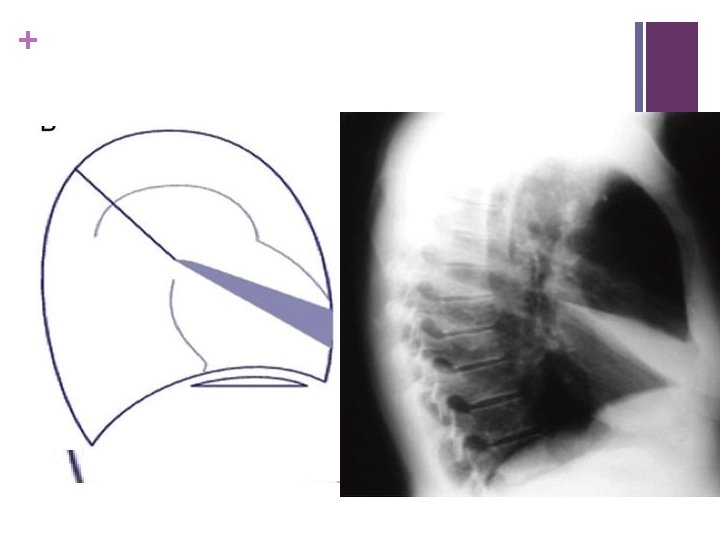

+ RML collapse – often missed, loss Rt heart border